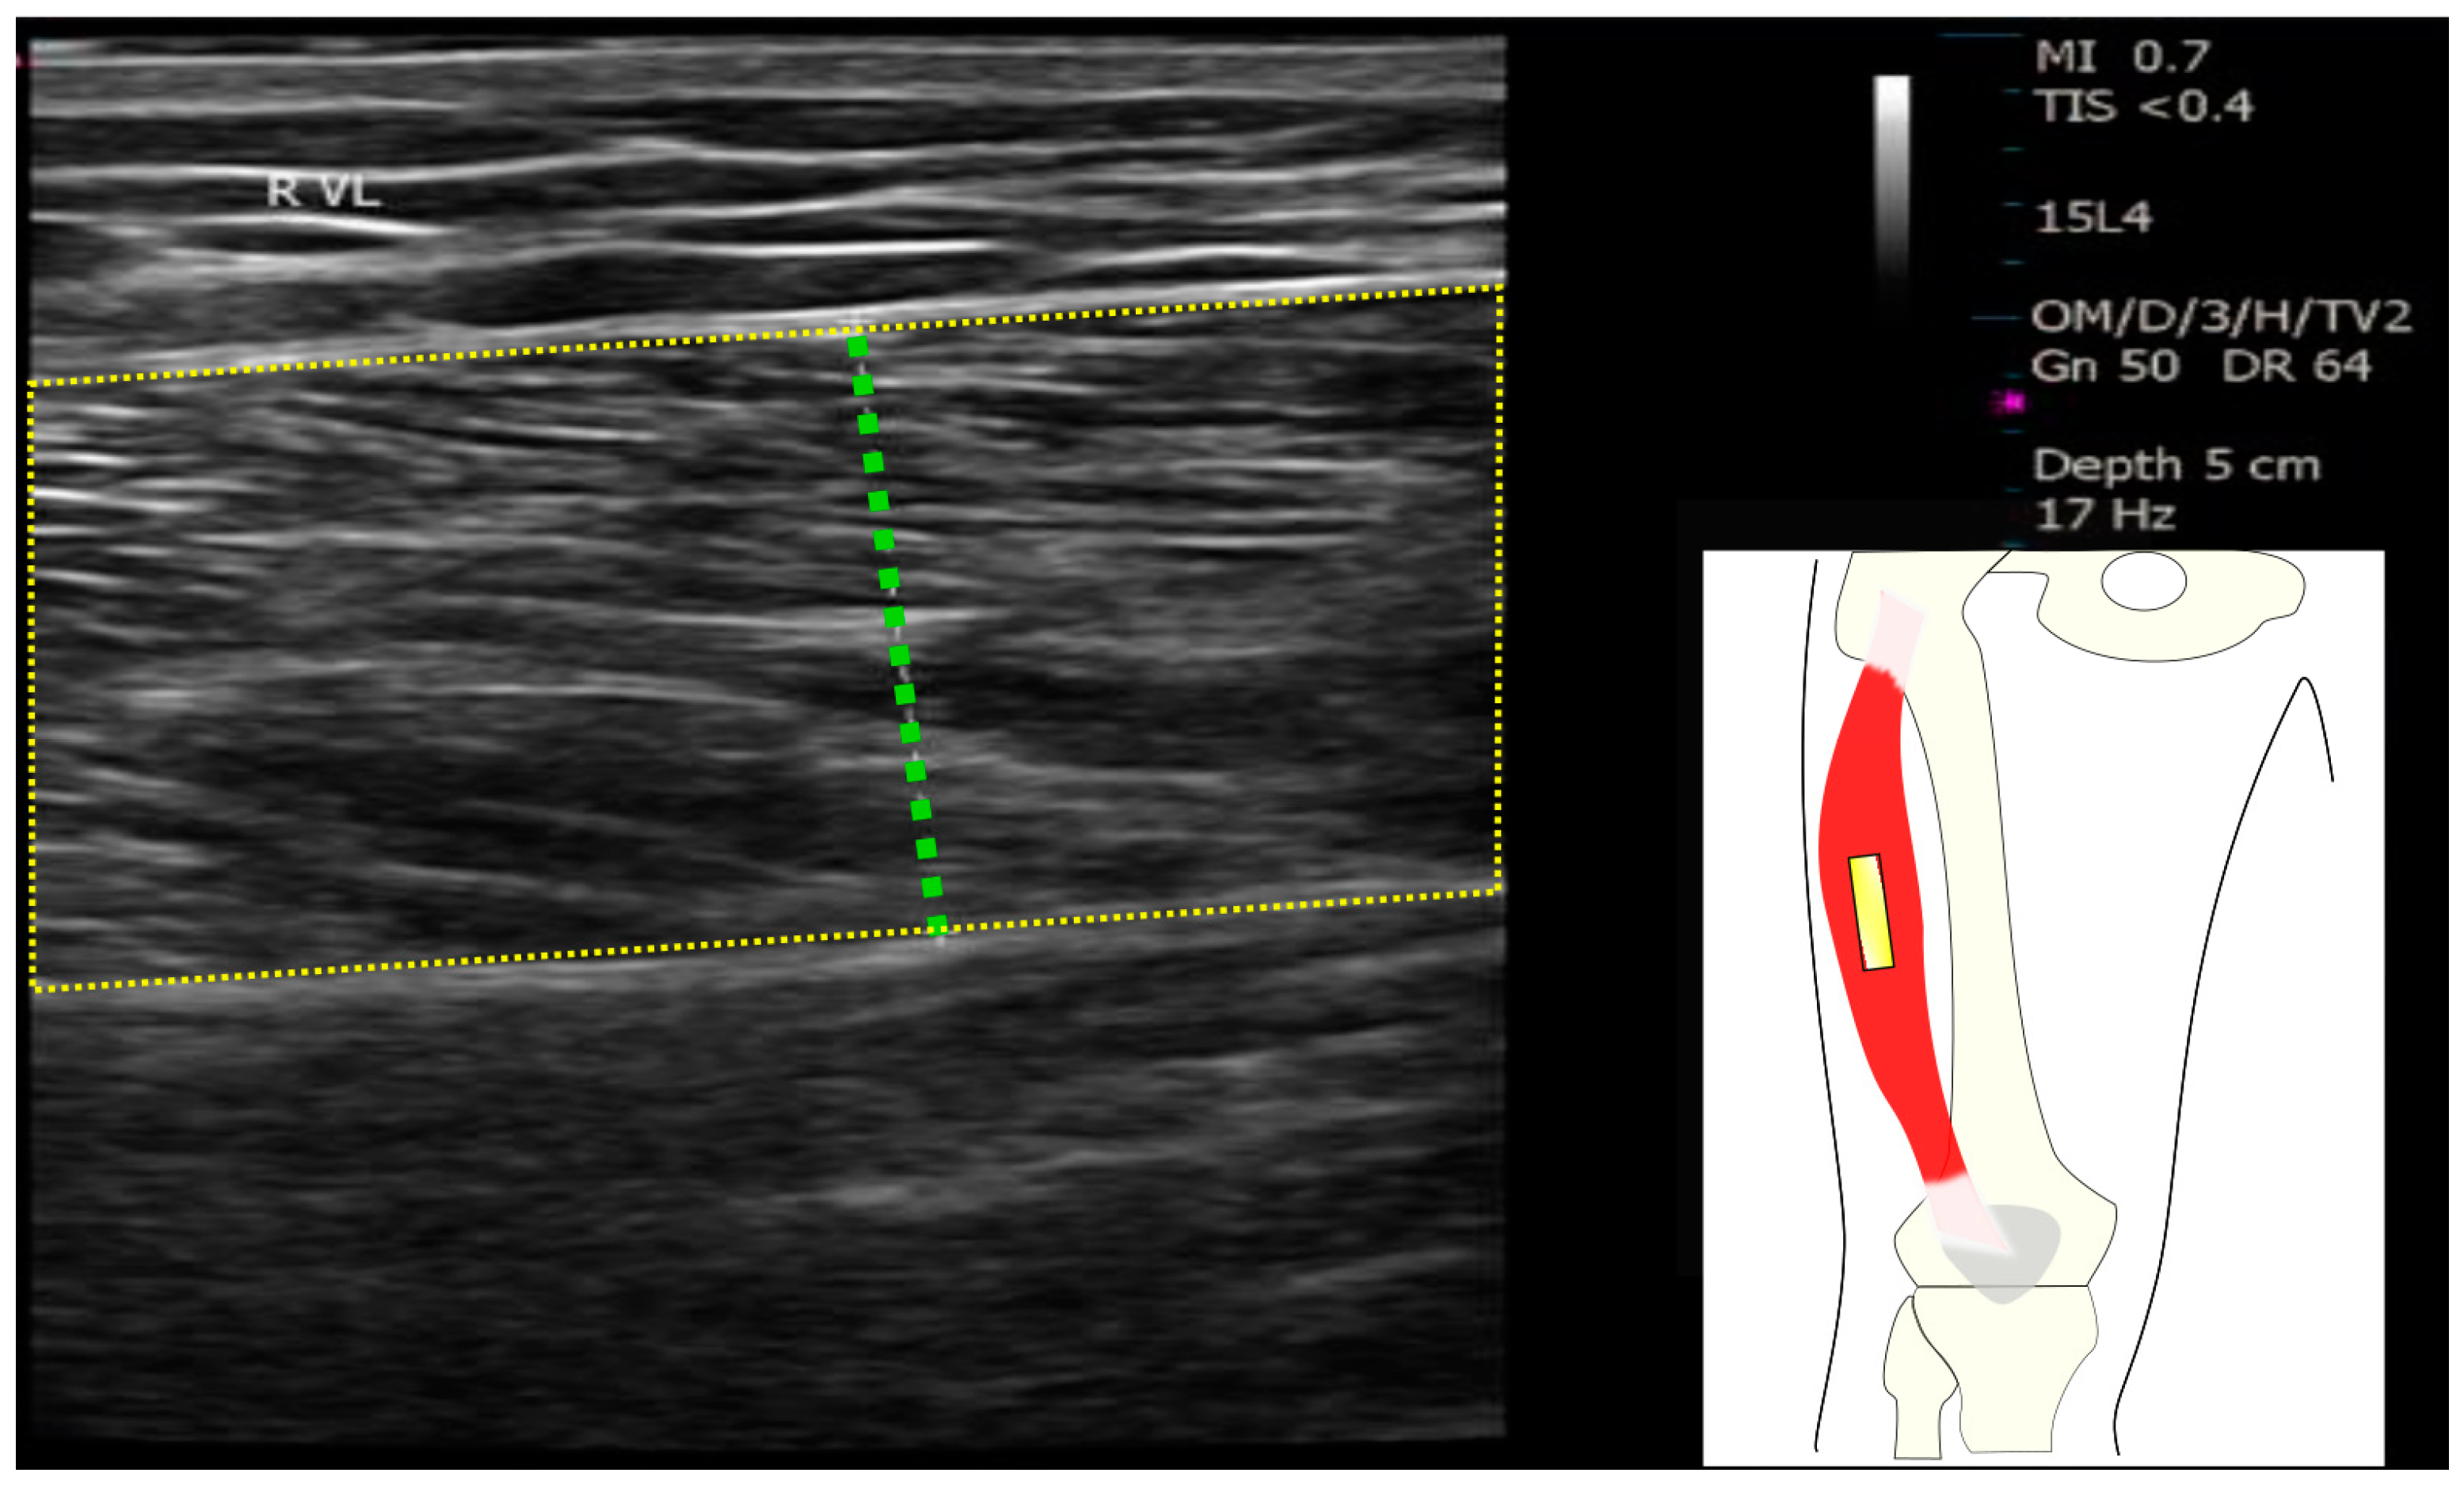

2.4. Muscle Ultrasound Measurements

- Ticinesi, A.; Narici, M.V.; Lauretani, F.; Nouvenne, A.; Colizzi, E.; Mantovani, M.; Corsonello, A.; Landi, F.; Meschi, T.; Maggio, M. Assessing Sarcopenia with Vastus Lateralis Muscle Ultrasound: An Operative Protocol. Aging Clin. Exp. Res. 2018, 30, 1437–1443. [Google Scholar] [CrossRef]